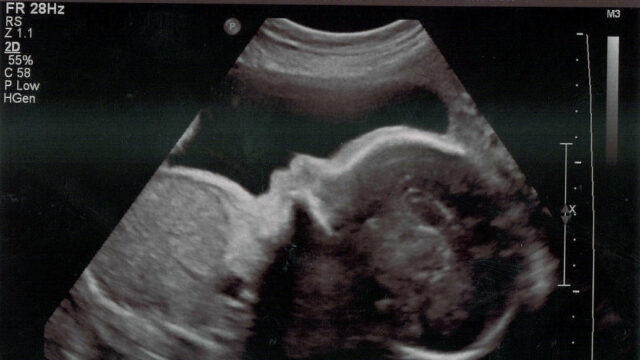

৩। আলট্রাসনোগ্রাফিঃ আমরা সকলে নিশ্চয় অবগত আছি যে আলট্রাসনোগ্রাফি এর আবিষ্কার আধুনিক চিকিৎসার ক্ষেত্রে অত্যন্ত গুরুত্ব পূর্ণ চিকিৎসা সেবার যন্ত্র। তাই এর ভূমিকা চিকিৎসা ক্ষেত্রে অপরিসীম।

আলট্রাসনোগ্রাফি সবার শুরুতে ব্যবহার করেন ১৯৩৭ সালে কার্ল ডুসিক এবং তার ভাই ফ্রেডরিখ। তারা ব্যবহার করেন মস্তিষ্ক গহ্বরের টিউমার সনাক্ত করতে। এর দ্বারা সাধারণত শরীরের ভেতরের অঙ্গ-প্রত্যঙ্গ, মাংস পেশি ইত্যাদির ছবি তোলা হয়।

এটি আসলে খুব উচ্চ কম্পাঙ্কেরে শব্দ ব্যবহার করে তার প্রতিধ্বনি কে শনাক্ত করা হয়। এর শব্দের কম্পাঙ্ক ১-১০ মেগাহার্টজ হয়ে থাকে এজন্য একে আলট্রাসনোগ্রাফি বলা হয়ে থাকে। এটির ছবি সাধারণত ২ডি অথবা ৩ডি হয়ে থাকে।

আলট্রাসনোগ্রাফি যন্ত্রে ট্রান্সডিউসার নামে একটি স্ফটিক থাকে। যা বৈদ্যুতিক শক্তি দিয়ে উদ্দীপ্ত করে উচ্চ কম্পাঙ্কের আলট্রাসনিক তরঙ্গ উৎপন্ন করা হয়। আলট্রাসনিক যন্ত্রে এই তরঙ্গকে একটা সরু বিমে পরিণত করা হয়। শরীরের ভেতরের যে অঙ্গটির প্রতিবিম্ব দেখার প্রয়োজন হয় ট্রান্সডিউসারটি শরীরের উপরের সে অংশে বিমটিকে শরীরের ভেতরে প্রবেশ করানো হয়, রোগী সে জন্য কোন ব্যথা বা অস্বস্তি বোধ করে না।

অতএব বলা যায় আধুনিক চিকিৎসা বিজ্ঞানে আলট্রাসনোগ্রাফির গুরুত্ব অপরিসীম।